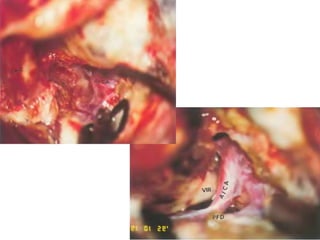

A nontoothed forceps is used to hold the soft tissues (ST) surrounding

the nerve at the level of the stylomastoid foramen (SMF), and

sharp scissors are used to dissect the soft tissues from the bone at that

level. C Cochlea, FN(m) Mastoid segment of the facial nerve, LSC Lateral

semicircular canal, NC New canal, SS Sigmoid sinus

Rerouting of the facial nerve. FN(m) Mastoid

segment of the

facial nerve, FN(p) Intraparotid facial nerve, SM

Facial nerve at the stylomastoid

level, ST Soft tissues

The facial nerve has been rerouted into the new

canal (*).

FC Fallopian canal, FN(p) Rerouted part of the

intratemporal facial nerve,

FN(t) Rerouted part of the tympanic segment of

the facial nerve, ST Soft

tissues